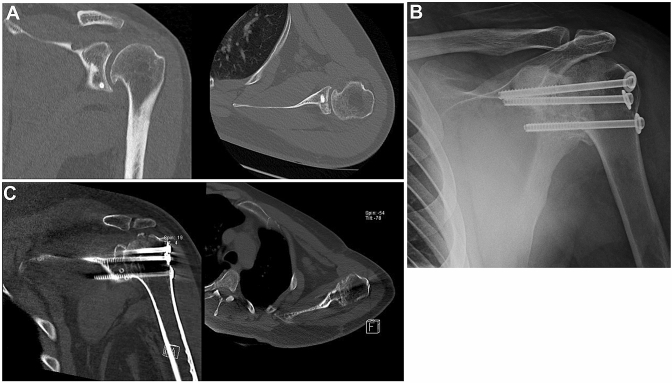

The authors preferred GHA technique depends on the selected patient and the hypothetical future conversion to a shoulder replacement (Table 1). When the indication is persistent refractory shoulder instability, inflammatory arthritis, or post traumatic early arthritis in the young patient and there is an intact rotator cuff, our preference is an open intraarticular GHA with screws (Fig. 2). Three cannulated 6.5 mm screws are placed under fluoroscopic control. In this procedure, the rotator cuff and acromiohumeral interface are spared. This will allow an easier conversion to shoulder arthroplasty in the future. When the indication is neurologic paralysis, inflammatory arthritis, septic arthritis or pseudoparalysis with combined rotator cuff and deltoid damage in the elderly patient, our preference is an open GHA using a plate fixation. Through an extended deltopectoral approach to the acromion and scapula spine, decortication of acromiohumeral and glenohumeral surfaces to bleeding subchondral bone is performed to increase the surface area available. The arthrodesis is fused by means of a 4.5 mm reconstruction plate over the spine, acromion and lateral humerus (Fig. 1). Regardless of the technique, our fusion position preference is 20–30º flexion, 10–15º abduction and 40–45º internal rotation. Also cortico-cancellous allograft from a fermoral head or tricortical iliac crest autograft is used to promote consolidation.

Fig. 2.

Case 2: a 25 year-old patient with recalcitrant post instability that after several failed stabilization procedures underwent GHA. a CT scan of the left shoulder showing coronal (left) and axial (right) projections of posterior screwed bone block procedure. Chronic instability led to early osteoarthritis with osteophytes in the infero-medial humeral head. b Radiograph of a left shoulder showing GHA using three cannulated screws with washers transfixing the glenohumeral joint. Fusion to the acromion was avoided. Post-operative CT scan of the left shoulder showing successful gleno-humeral fusion in coronal (left) and axial views (right)